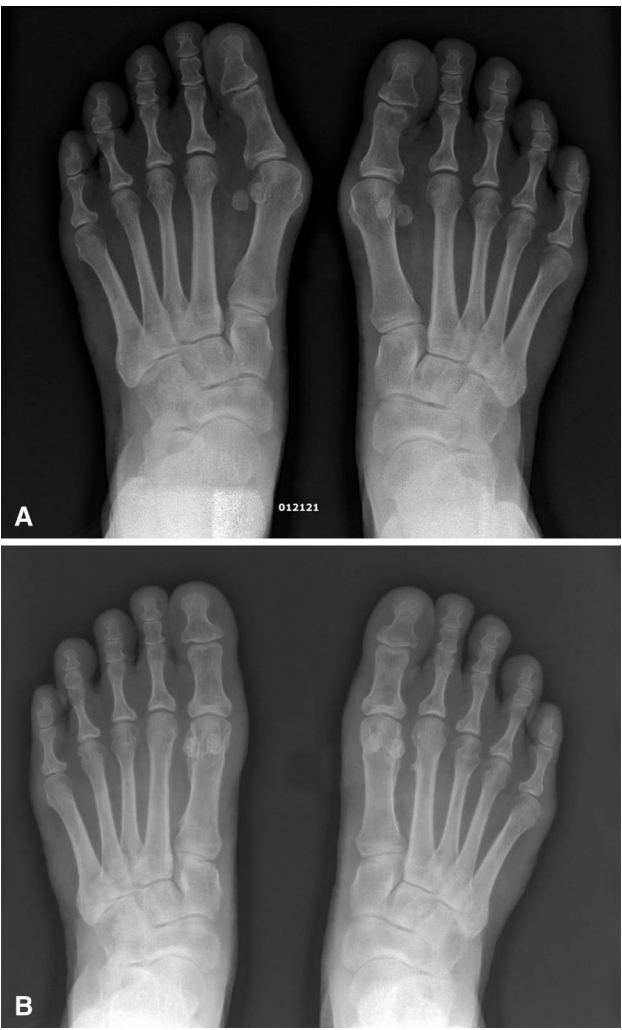

▲图示(A)一名 68 岁女性足部术前负重正位X线片:右足重度第一跖骨内翻畸形,伴第二趾重叠爪形畸形及跖趾关节背侧半脱位。(B)术后10天负重正位X线片:第一跖骨、拇趾、籽骨、跖趾关节及跖楔关节力线矫正良好,右足第二趾(含其跖趾关节)力线亦恢复正常。(C)术后6个月负重正位X线片:双足拇外翻及第一跖骨内翻畸形轻度复发,尤以右足跖骨间角为著,达 9.6°(超出正常范围)。(D)术后5年负重正位X线片:随访 4.5年,第一跖骨、拇趾、籽骨及第二趾力线无明显变化。(E)术后5年外观照:拇趾主动背伸活动功能良好。

拇外翻非截骨韧带联合术作为一种新型软组织矫正技术,以其非截骨、非关节融合、创伤小、术后恢复快、保留关节活动度等优势,在拇外翻矫正中展现出良好的临床疗效。该术式通过外侧软组织松解、第一跖骨环扎固定及诱导跖骨间软组织联合结构形成,可有效矫正拇外翻与MPV畸形,改善患者足部功能与临床症状,适用于中轻度拇外翻、合并跖骨内收畸形的拇外翻,以及截骨术后复发的病例。